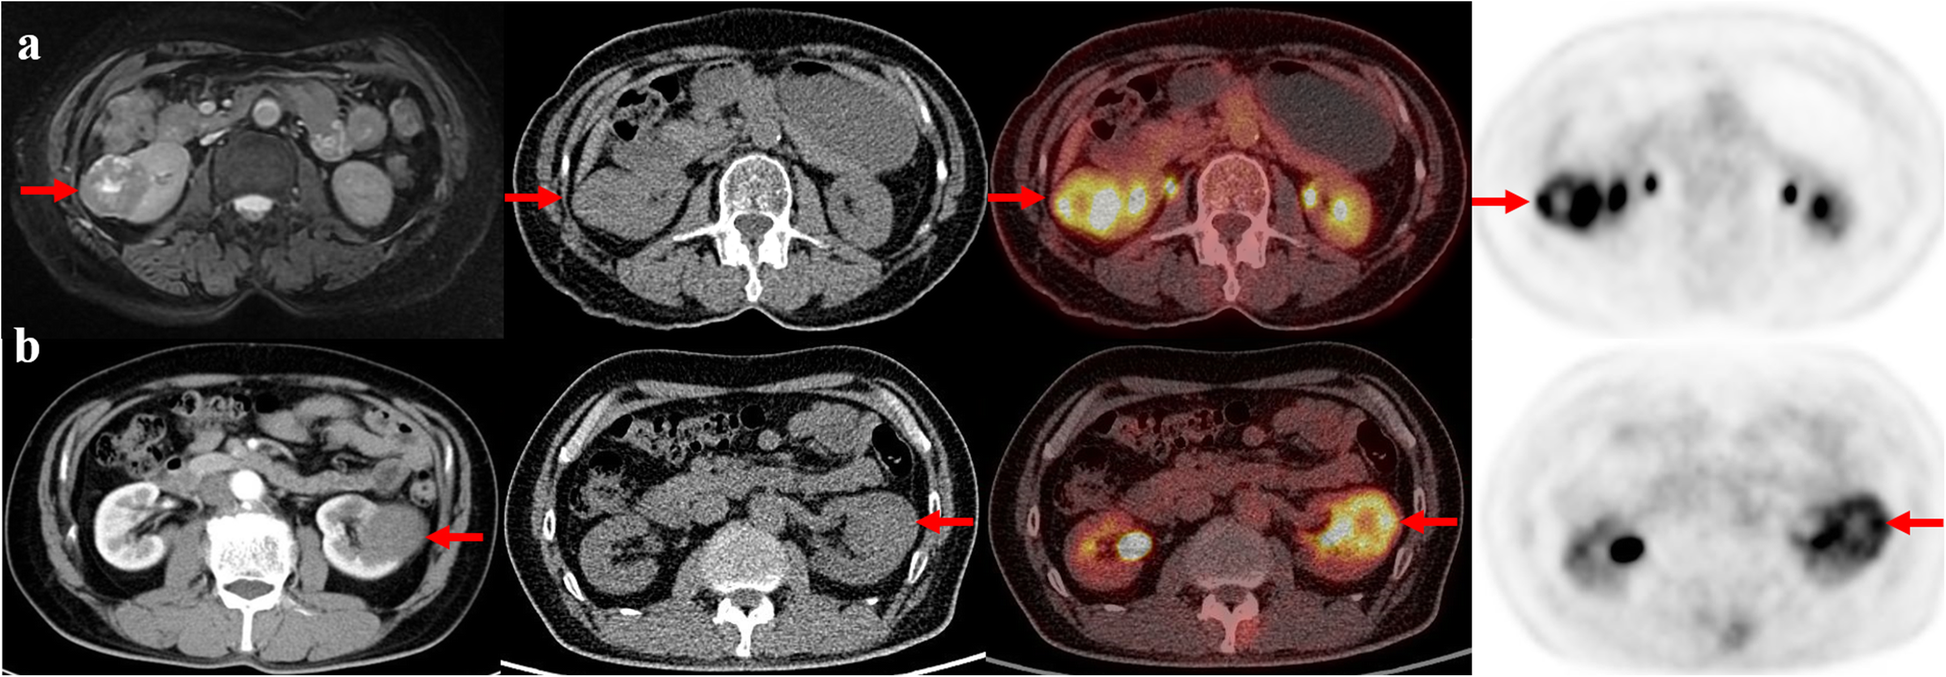

Representative cases. a The axial images from left-to-right are MR, coregistered CT, PET/CT fusion and PET. A 63-year-old woman with type 2 papillary renal cell carcinoma (WHO G3) in the right kidney (arrows). The primary tumor size is 4.4 cm, and the tumor SUVmax is 10.4. b The axial images from left-to-right are diagnostic contrast-enhanced CT, coregistered CT, PET/CT fusion and PET. A 61-year-old man with type 1 papillary renal cell carcinoma (WHO G2) in the left kidney (arrows). The primary tumor size is 4.2 cm, and the tumor SUVmax is 6